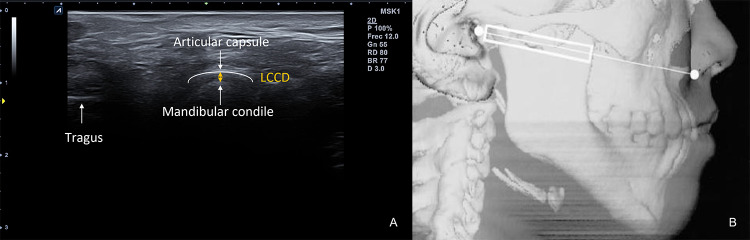

One examiner evaluated 72 TMJ of 36 Caucasian subjects who met the inclusion criteria. TMJ were assessed in a sitting position, in a closed mouth position and a neutral head and neck position. The examiner positioned the probe on an axial plane, running parallel to the Camper line (the line intersecting the ala of the nose and de tragus of the ear), perpendicular to the zygomatic arch, and parallel to the mandible ramus (Fig. 1). The probe was tilted to get the best view of the mandibular condyle and the TMJ. The dynamic movement of the TMJ was assessed in axial and coronal planes in closed-mouth and maximal open-mouth positions. Once the best image in the axial plane was obtained on the screen, it was recorded. All images were acquired with an Alpinion eCube i8 (Anyang-si, Gyeonggi-do, Ltd., Korea) with a 4 cm width linear transducer E8-PB-L3-12 T (frequency bandwidth 3–12 MHz) In the first round, the observer took one single LCCD measurement of the right and left joints as described by authors [14–16]. In a second round, one week later, the examiner evaluated the same 32 TMJ, but took three measurements of the LCCD, ensuring equal examination conditions. Each time he recorded the distance, he separated the probe from the subject's skin and restarted the process. For the study, researchers calculated the mean of these 3 measurements and compared them with the single measurement taken in the first round.

Fig. 1.

A US image obtained from the axial view. LCCD Lateral condyle-capsule distance. B US probe position schema. In: [16]. With the kind permission of the American Society of Neuroradiology